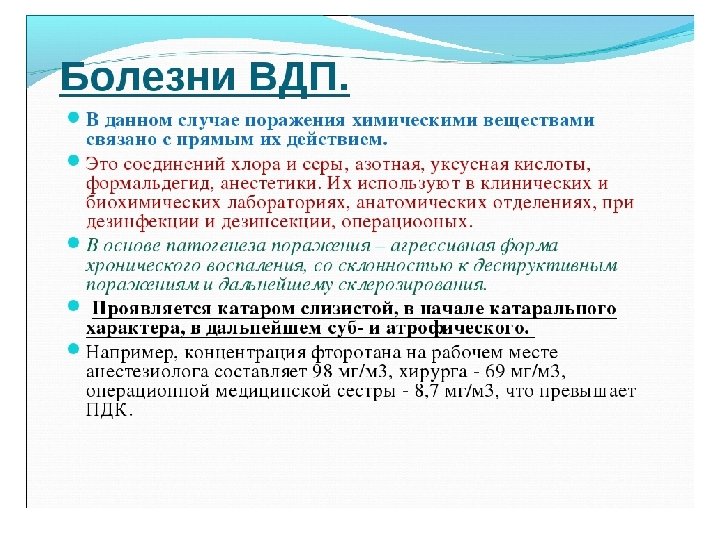

Самостоятельная работа (интерактив). Составление программ по управлению факторами риска развития профессиональной патологии. В роли эксперта специалиста по медицине труда выступает группа обучающихся. 2 Кейса: 1. Программа по управлению профессиональными факторами риска офиса (банковские служащие) 2. Программа по управлению факторами риска в клинической научно исследовательской лаборатории (химические реактивы, биологические жидкости, подопытные животные, микроскопия.